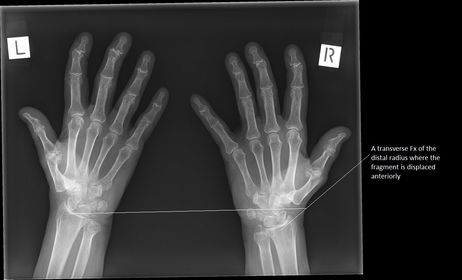

1. Bennett's Fx 2. Boxer's Fx 3. Barton's Fx 4. Colle's Fx

Smith's Fx